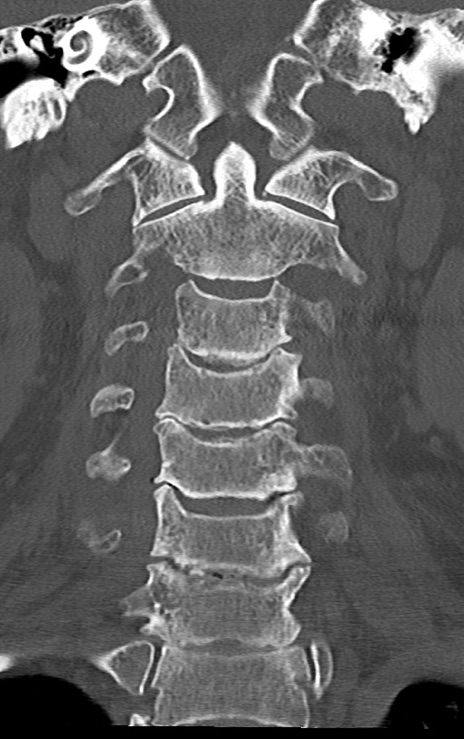

頚椎CT

矢状断像